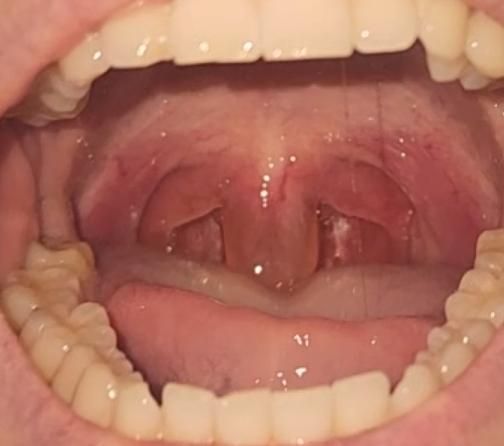

목젖이 뚱뚱해지고 투명해졌어요....

목이 침삼킬때 아프더니

목젖이 투명해지고 뚱뚱한 젤리가 되었는데

이거 왜그런건가요

심각한 문제인가요?...........

목젖은 점막으로 되어 있어 염증 등에 의해서 쉽게 부어오르거나 할 수는 있습니다. 다만 해당 소견만으로는 정확한 원인 감별 및 진단 등이 가능하지는 않습니다. 바이러스 감염, 역류성 식도염, 비염 및 후비루, 알러지 반응, 기계적인 자극 등 여러가지 요인들이 관련이 있을 수 있습니다. 증상과 관련하여서는 혹시 모르므로 한 번 이비인후과적으로 괜찮은지 진료 및 검진을 받아보는 것이 도움이 될 수도 있겠습니다.